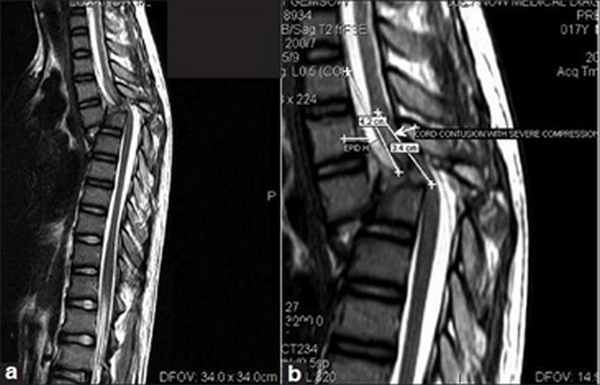

МРТ. Этот метод полезен для выявления признаков повреждения спинного мозга кровоизлияний и других морфологических изменений в мягких тканях.